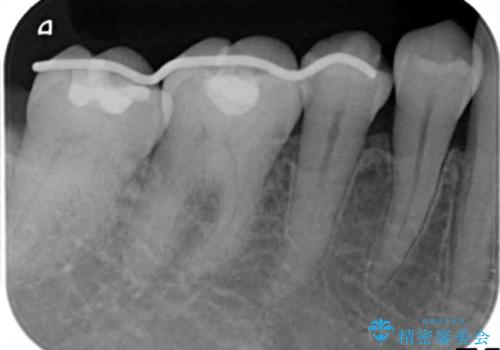

X線検査、歯周組織検査より歯の周囲の骨が溶ける歯周病であることがわかりました。

歯を抜かずに残せるよう、再生療法・歯周ポケット除去手術を計画します。